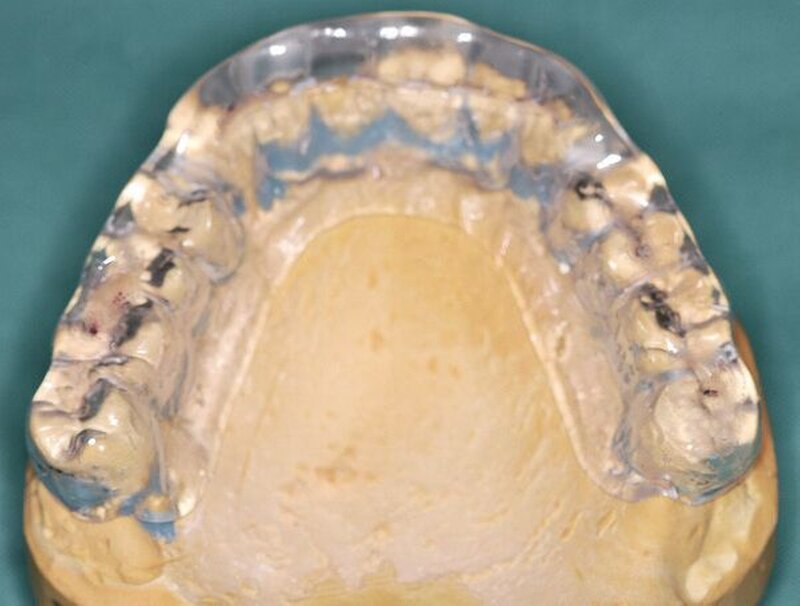

Nach einer fünf Monate dauernden Funktionstherapie mit Stabilisierungschiene und initial begleitender manueller Therapie wurde aufgrund der vollständigen Beschwerdefreiheit mit den weitergehenden Behandlungsmaßnahmen begonnen. Zunächst wurde die Schiene im Bereich der Zähne 11/12 in zwei Teile separiert. Die Zähne des IV-Quadranten wurden mittels dentinadhäsiver Aufbaufüllungen rekonstruiert und – bei im II-Quadranten eingesetzter Schiene – reokkludiert. Nach Abschluss dieser Maßnahme wurde die Dentition im III-Quadranten auf die gleiche Weise aufgebaut und reokkludiert. Durch dieses Vorgehen war es möglich die Schienenokklusion, bei gleichzeitiger Anfertigung von dentinadhäsiven Aufbaufüllungen im Unterkiefer, auf diese zu übertragen, so dass der Patient auch ohne Schiene in identischer horizontaler und vertikaler Kieferrelation abgestützt war. Nach einem Zeitraum von 14 Tagen bestand noch immer vollständige Beschwerdefreiheit, so dass beschlossen wurde, mit der Behandlung fortzufahren.

In der folgenden Sitzung wurden Versorgungsabformungen des Ober- und des Unterkiefers unter Verwendung eines A-Silikons angefertigt. Danach wurden alle verblockten Kronen sowie die Brücken im Oberkiefer entfernt. Die Zähne 14, 13, 12, 21, 22, 23 und 24 wurden exkaviert und mittels dentinadhäsiver Füllungen aufgebaut, danach präpariert. Im Anschluss wurden die Zähne 17 und 27 extrahiert. Da im vorliegenden Fall für den Zeitraum der Wundheilung sowie für die zur Anfertigung des Zahnersatzes notwendige Zeitspanne keine herausnehmbaren Provisorien gewünscht wurden und klare finanzielle Vorgaben gesetzt waren, wurde ein chairside gefertigtes, direktes Kunststoffprovisorium mithilfe der zuvor erstellten Versorgungsabformung im Sinne einer Anhängerbrücke 15 bis 25 angefertigt und mittels provisorischen Zements eingegliedert.